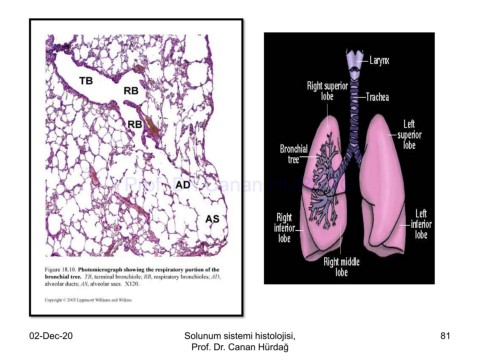

Page 81 - Solunum Sistemi